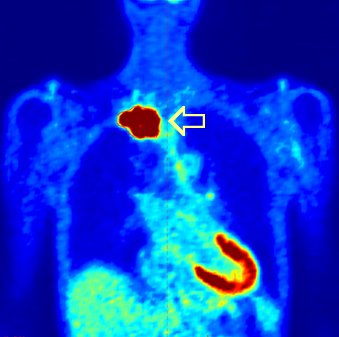

What makes Pancoast tumors unique is that the patient often presents with severe pain and neurologic symptoms but minimal lung symptoms often delaying making the correct diagnosis. CT scans and MRI scans are usually markedly abnormal (go here and here). More CT scans here, here, here

The overwhelming majority of cases of Pancoast syndrome are non–small cell lung carcinoma (NSCLC), with more than 95% located in the superior sulcus, go here. The most common varieties are squamous cell carcinoma or adenocarcinoma. Small cell carcinoma is observed in fewer than 5% percent of cases in most series.